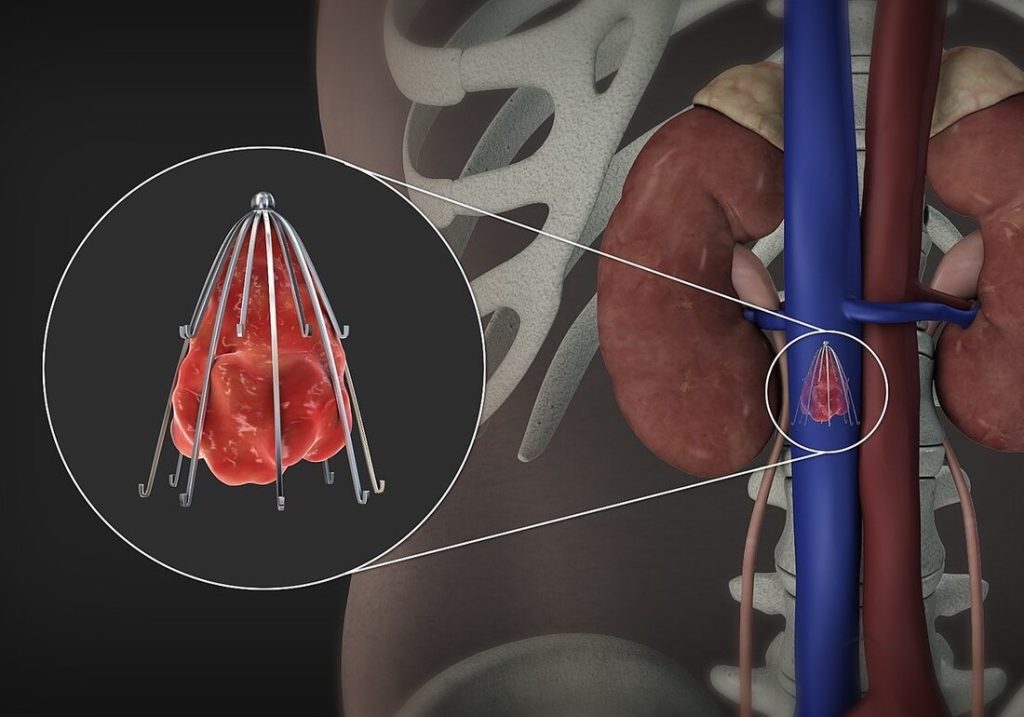

فیلتر ivc قلبی یا فیلتر ورید اجوف تحتانی (Inferior Vena Cava Filter یا IVC Filter) یک دستگاه پزشکی کوچک است که در ورید اجوف تحتانی (IVC) قرار میگیرد تا لختههای خون را قبل از رسیدن به ریهها گیر بیندازد و از آمبولی ریوی (PE) جلوگیری کند. این فیلترها عمدتاً برای بیمارانی استفاده میشوند که VTE (ترومبوآمبولی وریدی) دارند اما نمیتوانند از ضد انعقادها استفاده کنند، مانند موارد خونریزی فعال یا جراحیهای پرخطر.

• وایر نازک وارد ورید میشود و تحت فلوروسکوپی به IVC هدایت میشود. - ونوگرافی (Cavography):

• کاتتر چندسوره وارد میشود.

• ماده حاجب تزریق میشود تا آناتومی IVC، قطر آن، موقعیت وریدهای کلیوی (renal veins) و وجود لخته بررسی شود.

• موقعیت ایدهآل فیلتر: درست زیر وریدهای کلیوی (infrarenal) برای جلوگیری از انسداد

• sheath (لوله بزرگتر) روی وایر پیشرفته میشود تا به موقعیت مورد نظر برسد. - باز کردن (Deployment) فیلتر ivc قلبی:

• فیلتر فشردهشده داخل sheath推進 میشود.

• sheath عقب کشیده میشود تا فیلتر باز شود و با قلابها یا پاها به دیواره IVC بچسبد.

- قرارگیری suprarenal (بالای وریدهای کلیوی): در بارداری، ترومبوز infrarenal یا آناتومی غیرعادی.